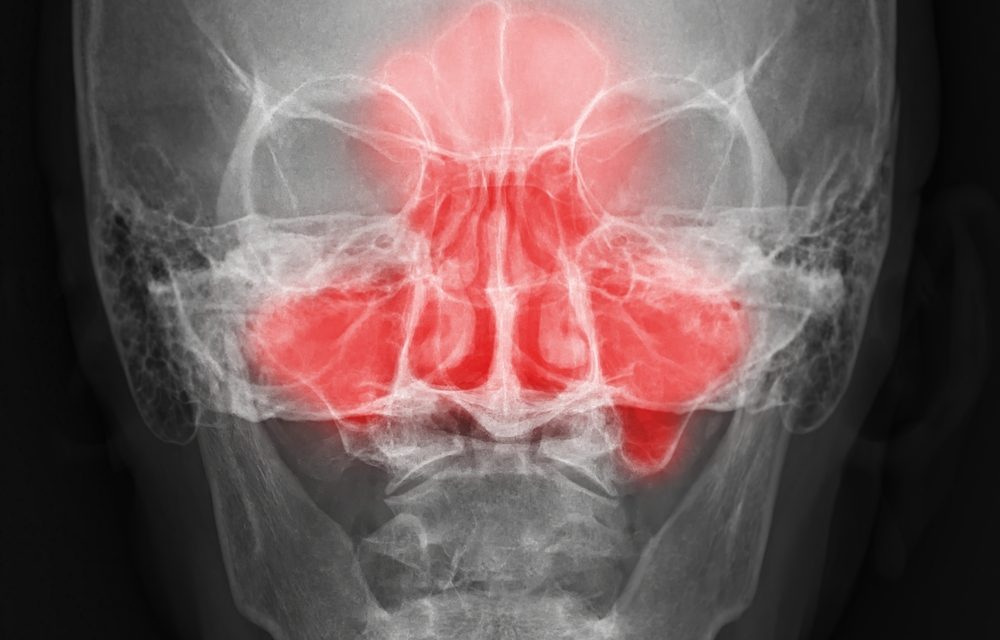

An estimated 34 million Americans experience sinus-related symptoms. In many cases, an upper respiratory infection can obstruct the sinus ostia, limiting normal drainage. When drainage is impaired, mucus can accumulate within the sinus cavities, creating conditions that may allow bacteria to proliferate. Clinically, this may resemble a prolonged or recurrent cold.

Chronic sinusitis is commonly associated with pressure or discomfort between the eyes, along the sides of the nose, or in the forehead. Individuals may report nasal congestion, headaches, nasal discharge, sore throat, or coughing related to postnasal drainage. Some people describe experiencing multiple “colds” in close succession, which may reflect persistent rather than separate episodes. A nonproductive cough or throat irritation related to mucus drainage is also frequently reported.